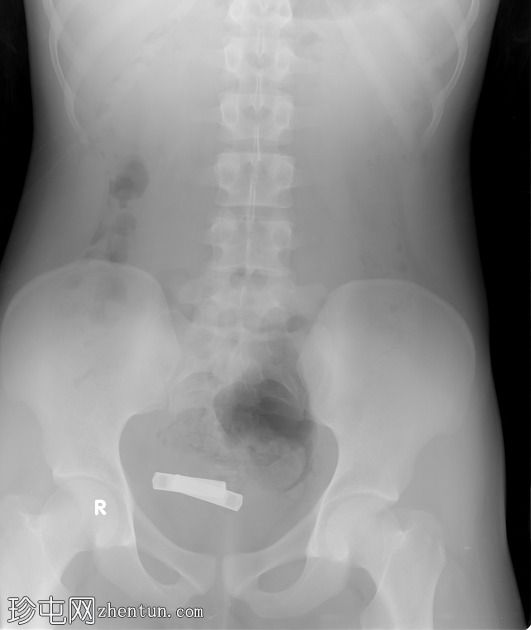

2.jpeg

正位片

盆腔内可见两个不透射线的异物。